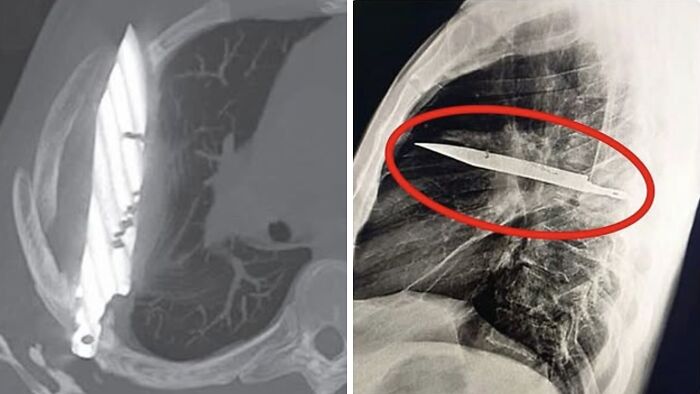

Un hombre de 44 años llegó al hospital con una extraña herida en el pecho. Durante el examen, los médicos descubrieron que una hoja de cuchillo llevaba ocho años alojada en su pecho, sin que él lo supiera.

Resulta que lo apuñalaron hace años y le cosieron la herida sin examinarla a fondo. Desde entonces, vivió con normalidad, sin síntomas especiales, hasta que la herida empezó a sangrar y una radiografía reveló la hoja oculta.

La hoja fue extraída quirúrgicamente, el paciente se recuperó y recibió el alta a los pocos días.